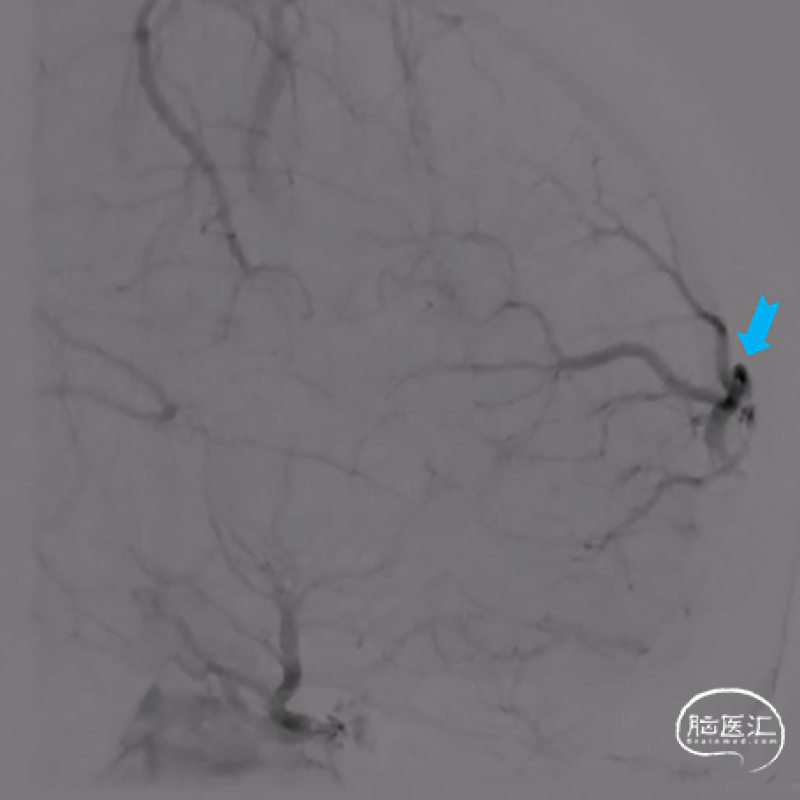

造影提示左侧前颅底眼动脉末端分支供血的DAVF经矢状窦起始段回流,回流静脉迂曲,局部可见粗大的静脉球。

侧位造影

斜位病灶局部造影

局部造影显示瘘口三要素:供血动脉(红色箭头),瘘口及引流静脉(静脉球),其中蓝色箭头所示静脉期正常回流静脉。